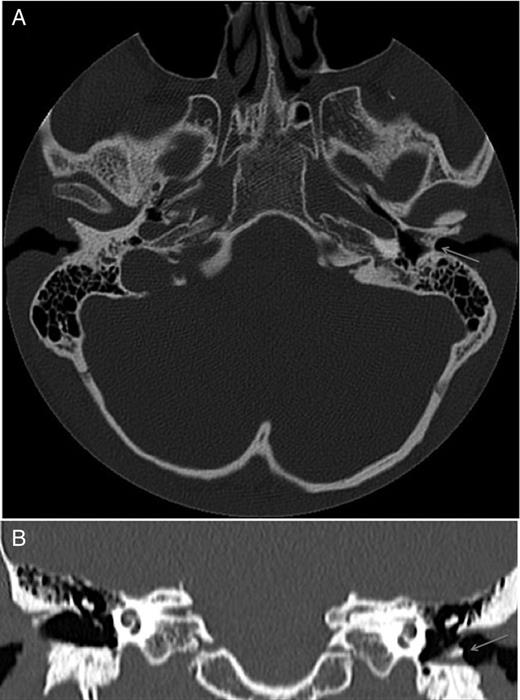

On assessment, he denied otorrhoea or other otological symptoms. His general medical history was unremarkable. His left tympanic membrane had a normal anterior appearance, but the posterior half of the external auditory canal was obliterated. His right ear was unremarkable, except for a patch of myringosclerosis. Audiometry revealed a right mild high tone sensorineural hearing loss (presumed secondary to previous otitis media) and a left severe mixed hearing loss (pure tone average 79 dB) associated with a type B tympanogram. CT imaging confirmed a normal middle ear cleft, with a plug of soft tissue containing dense calcification 8 mm lateral to the tympanic membrane (Fig. 1), consistent with a diagnosis of left chronic fibrosing otitis externa.

CT temporal bone axial (A) and coronal (B) slices, demonstrating a soft tissue thickening of the left medial external auditory canal containing dense calcification (arrow).